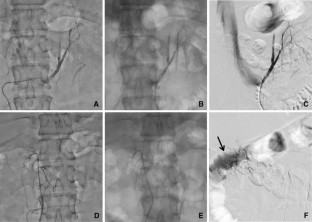

Fig. 1